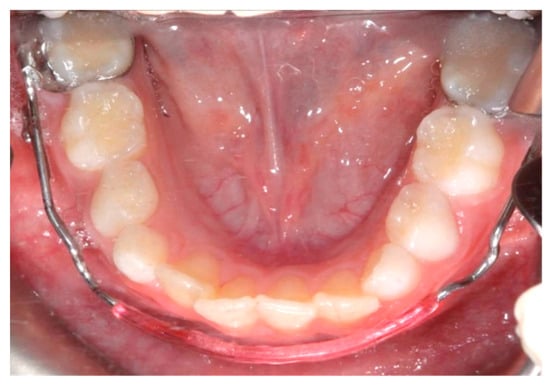

The lower jaw is considered the guiding arch in crowding therapy because it is difficult to modify its perimeter due to the more compact bone structure and the continuity with the mandibular branch, which does not allow for distalization [37,41]. In addition, the symphysis cartilage ossifies in the first year of life, so it is not possible to perform an orthopedic bone expansion, as in the upper jaw, working at the level of the median palatine suture [41,42]. The modalities of space recovery in mixed dentition are: arch perimeter increment, reduction in mesiodistal widths of teeth and serial extractions [2,43,44]. In the upper arch, the expansions are quite stable, but inferiorly, it is universally recognized that the expansion of the intercanine diameter always recurs, whereas expansion at the molar level is quite stable, which should be considered [27,45,46,47]. The space that can be recovered in the lower arch depends on the type of sector: in general, in the posterior sector, utilizing a lip bumper-style device, it is possible to recover a maximum of 2 mm of space per molar distalization in the posterior regions. At the molar level in the lateral sectors, the arch length could increase by about 0.4 mm; at the canine level, the arch length increases about 0.7 mm [48]. The vestibularization of one millimeter of the incisal margin in the anterior sector results in the gain of one millimeter of arch space, or roughly a ratio of one to one (changing the arch form) [47]. Schwarz’s appliance (Figure 3) and lip bumper (Figure 4) are two commonly used appliances for increasing lower dental arch dimensions [49]. In their study, Vincenzo Quinzi et al. compared the effects of these appliances on reducing mandibular crowding by increasing lower arch dimensions [27]. The study included twenty subjects (10 males and 10 females). Ten patients were treated with Schwarz’s appliance, and ten with lip bumper. The Schwarz appliance was more effective in increasing intercanine arch dimensions and arch perimeter, although the lip bumper reached a greater increase in arch length [27]. Since the 1970s, there have been reports of spontaneous changes in mandibular dentition caused by maxillary expansion [31,50]. Di Ventura et al. assessed the consequences of rapid maxillary expansion (RME) anchored to primary molars on the mandibular arch. A total of 54 patients were recruited for this study and divided into two groups: a test group (21 patients, 7.4 ± 1.2 years) who underwent RME, and a control group (17 patients, 7.3 ± 1.1 years old) who did not receive any treatment. The results of this study showed a significant increase in interdental width in the lower arch after 9 months of RME therapy [31]. Olivia Griswold et al. evaluated the changes in sagittal mandibular incisors’ position in response to lip bumper therapy using CBCT [32]. In this study, the authors compared a group that was treated only with rapid maxillary expansion (experimental group) and an RME + LB (lip bumper) group (control group) [32]. The CBCTs were placed in 3D on the mandibular structure, and the angular and linear alterations in the mandibular incisors throughout LB therapy were assessed. In the investigation, there was no statistically significant difference in the degree of mandibular incisor protrusion between the two groups; the lip bumper did not generate substantial proclination, protrusion or extrusion of the mandibular incisors. [13]. Air-rotor stripping (ARS) (Figure 5) is a technique for creating space during the mixed dentition period by reducing interproximal enamel thickness. Yahya B. Nakhjavani et al. assessed the efficacy of the mesial stripping of mandibular deciduous canines for the correction of rotated and lingually erupted lateral incisors in 42 patients with <3 mm mandibular crowding [33]. In this study, the mesial stripping of mandibular primary canines resulted in full crowding correction; in just few cases, the amount of crowding did not reach zero, and a small crowding in the range of 0.06 to 0.1 mm remained [33]. The extraction of all the first premolars with subsequent orthodontic treatment is the most used method to relieve dental crowding [51]. The importance and timing of extraction as a component of orthodontic therapy for late incisor crowding have been well investigated [35]. No difference in late incisor crowding is shown by the data, regardless of whether serial extraction or early or late premolar extraction is performed prior to orthodontic treatment. Additionally, selecting a non-extraction orthodontic procedure has been linked to post-retention crowding [35]. Maurits Persson et al. investigated changes in the mandibular incisor area from early adolescence to late adulthood in patients with a class I crowding malocclusion treated in the mixed dentition by the extraction of all first premolars without subsequent orthodontic treatment [35]. The extraction group included 24 subjects who had all their first premolars extracted at a mean age of about 11.5 years to treat a class I space deficiency malocclusion. The control group included 21 subjects who had normal occlusions at the age of 13 years [35]. The extraction group showed no improvements in lower incisor irregularity, and a significant increase in lower tooth space insufficiency into adulthood. Lower incisor irregularity and space shortage developed significantly in the control group throughout late adulthood [35]. Premolar extraction is the sole treatment option for severe crowding in a class I occlusion, allowing for spontaneous adjustments and more stable incisor alignment in late adulthood, according to the authors [35] (Table 2).

Figure 5. Air-rotor stripping (ARS).